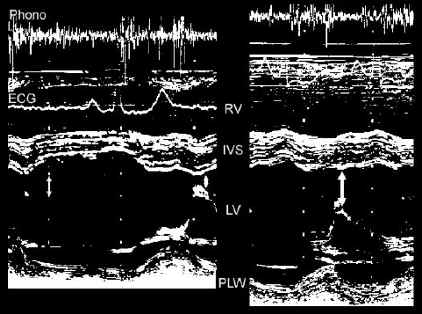

M-Mode examination of the left ventricle

Left panel

: normal LV

Right panel: dilated LV with reduced systolic function. Fractional shortening is 21 %. Note hypokinesis of the interventricular septum.

Note increased mitral E-septum separation on the right, as compared to the normal LV.

IVS

: interventricular septum

LV: left ventricular cavity

Phono: phonocardiographic tracing

PLW: postero-lateral wall

RV: right ventricular cavity

Measurement units: cm